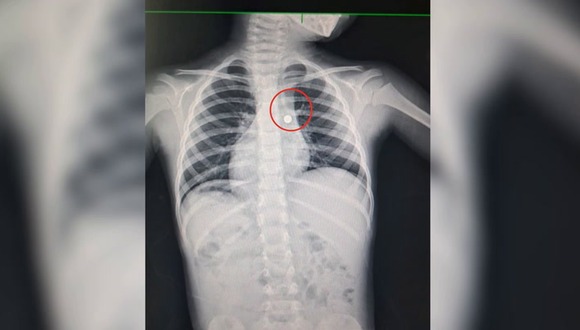

Los neumólogos le realizaron diversos exámenes como radiografía y tomografía, que revelaron que el menor tenía, en el bronquio del pulmón derecho, una pila de reloj de 8 milímetros.

“Tenía una pila en el bronquio derecho; por ello, fue llevado a sala de operaciones, donde le realizamos la extracción del cuerpo extraño y la limpieza del líquido del ácido que dejó esta batería en el bronquio”, señaló el médico.